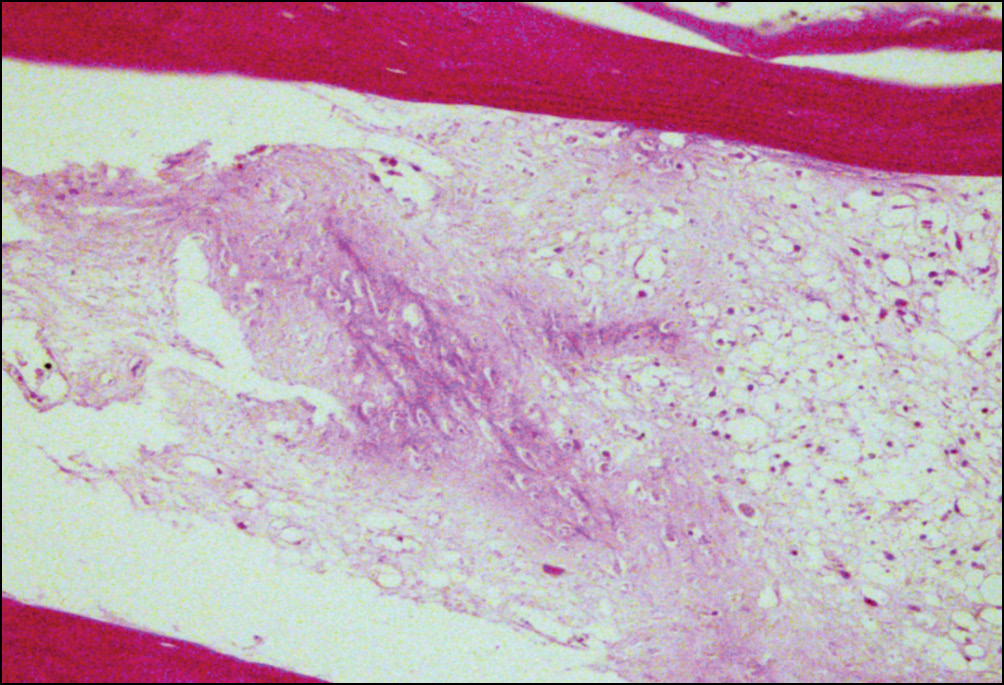

Вместе с тем, в участках, построенных из зрелых костных балок, выявляли очаги хондроидной метаплазии основного вещества, волокнистого строения (рис. 3).

Рис. 3. Репаративные изменения костной ткани в зоне перипротезных переломов бедренного компонента: между зрелыми костными балками участок хондроидной метаплазии основного вещества костной ткани, волокнистого строения. Окраска по Ван Гизону. Увел. ×160

Fig. 3. Reparative changes in periprosthetic fractures bone tissue of the femoral component: between the mature bone trabeculae — a section of chondroid metaplasia of bone tissue basic substance of fibrous structure. Staining according to Van Gieson. Magnification × 160